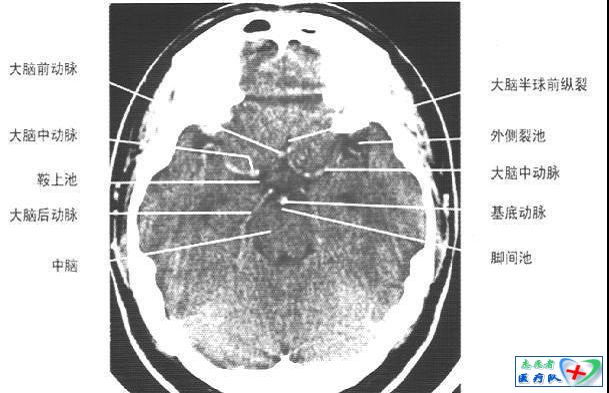

照片描述:鞍上池层面(平扫)

照片描述:鞍上池层面(增强)